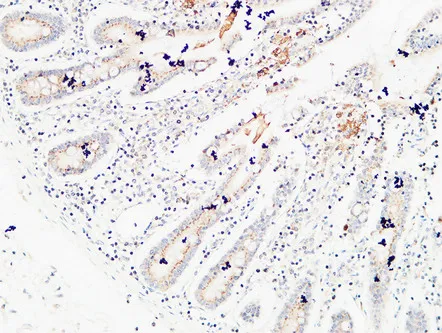

E-Selectin Rabbit Polyclonal Antibody

Cat: APRab10626